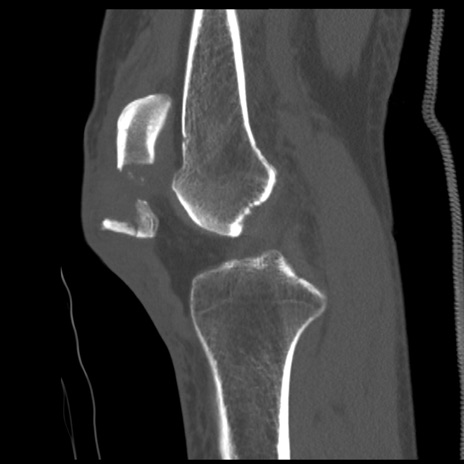

症例28 右膝関節CT(矢状断像)

右膝関節CT

冠状断像